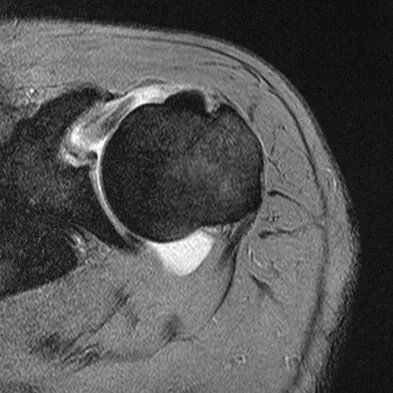

A 47-year-old male tennis player has pain in his nondominant shoulder that has failed to respond to 4 months of nonsurgical management. Examination reveals acromial tenderness and pain at the supraspinatus tendon insertion. He has a positive impingement sign, pain on forward elevation, and minimal cuff weakness. The MRI scans are shown in Figures 30a and 30b. To completely resolve his symptoms, treatment should consist of

Explanation

The MRI scans show a mesoacromion with tendonopathy of the supraspinatus. The history and physical findings indicate that the patient has a symptomatic os acromiale. Simple excision of the unstable os acromiale has not yielded consistently good results. Meticulous internal fixation using tension banding with cannulated screws and autologous bone grafting has shown good results for this problem. Hutchinson MR, Veenstra MA: Arthroscopic decompression of shoulder impingement secondary to os acromiale. Arthroscopy 1993;9:28-32.